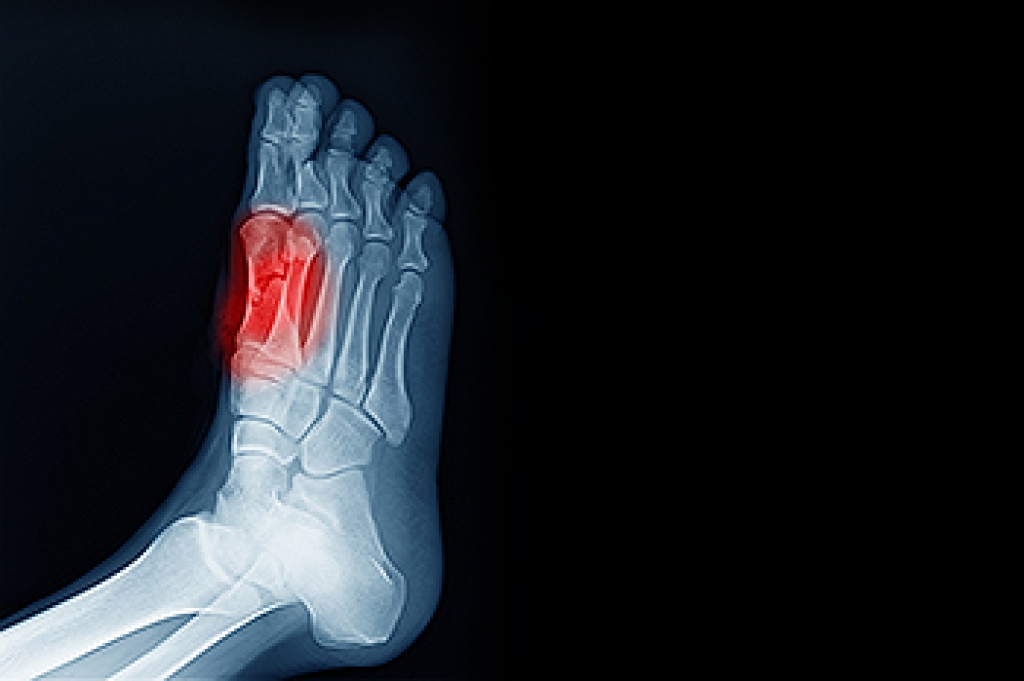

One has flat feet when one or both feet have fallen arches. Flat feet are common in babies and young children as part of normal growth and development of the foot and often do not cause symptoms. Flat feet in adults can have numerous causes, including weak or torn tendons, deformities from rheumatoid arthritis, broken bones in the middle of the foot, and injuries to ligaments. As one becomes older and more active, pain from flat feet can be felt in the heels or arches of the feet or even in the knees, hips, and lower back after prolonged standing, walking, or activity. Those with weight problems, diabetes or who are pregnant are more apt to feel discomfort from flat feet. If any kind of ongoing pain develops in the feet or ankles, visiting a podiatrist can help diagnose and treat the problem. If flat feet are suspected, the podiatrist may recommend lifestyle changes, rest, stretching exercises, physical therapy, more supportive shoes, arch supports, and over-the-counter pain medications.

Flatfoot is a condition in which the arch of the foot is depressed and the sole of the foot is almost completely in contact with the ground. About 20-30% of the population generally has flat feet because their arches never formed during growth.